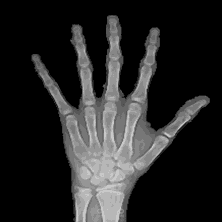

- طوّرتُ نظام تعلّم آلة للتنبؤ بالعمر العظمي

- استخرجتُ الميزات ودرّبتُ النموذج